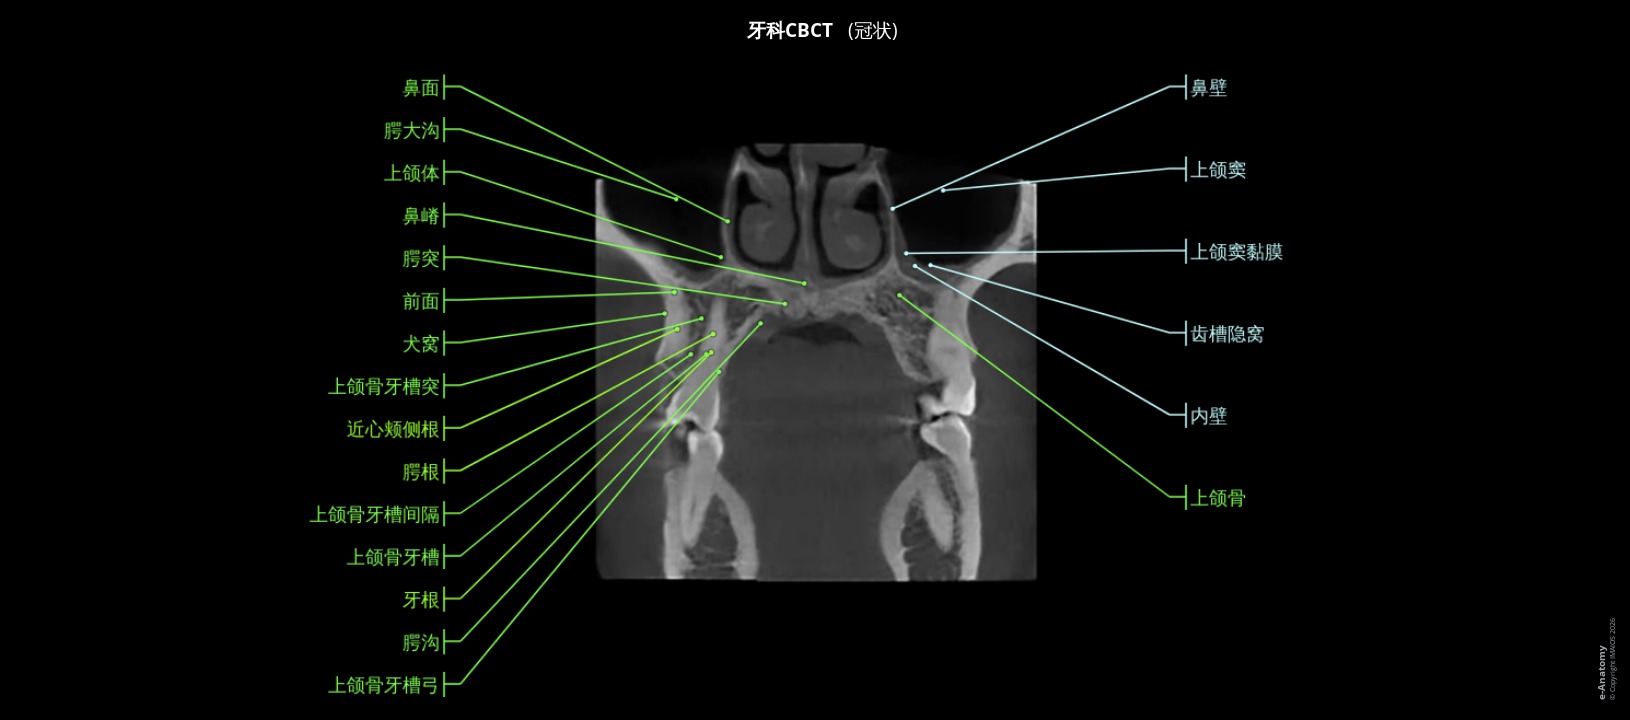

注意!此项检查缺少上颌和下颌第三磨牙。

牙科锥形束计算机断层扫描 (CBCT) 检查已被广泛接受,可用于几乎所有牙科领域的临床应用。

牙科CBCT允许牙科专家(牙医、口腔颌面外科、人工植牙和牙髓病学):

- 评估底层骨骼结构,以及神经通路和周围软组织

- 显示潜在的牙齿问题,例如蛀牙、骨质流失、异常生长、面部骨折、牙周感染、颞下颌关节不规则以及牙根或牙髓问题。

- 计划人工植牙。

- 提供准确的测量值,包括下颌骨的形状和尺寸。

- 识别牙龈问题。

- 评估鼻窦和鼻腔。

此牙科CBCT由Antoine Micheau医学博士(法国蒙彼利埃放射科医生)使用 ProMax 3D Planmeca对一名男性患者进行。

可惜的是上颌和下颌第三磨牙缺失(小时候第三磨牙被移除)。

根据日常生活中最常用的那些选择成像平面和重建:正交(横向)、矢状和正面平面、带有牙齿横截面的弯曲MPR重建和全景(正断层摄影)重建、骨结构的三维容积透视。

解剖结构是由Antoine Micheau医学博士(法国蒙彼利埃放射科医师)根据Terminologia Anatomica 1所标记的。